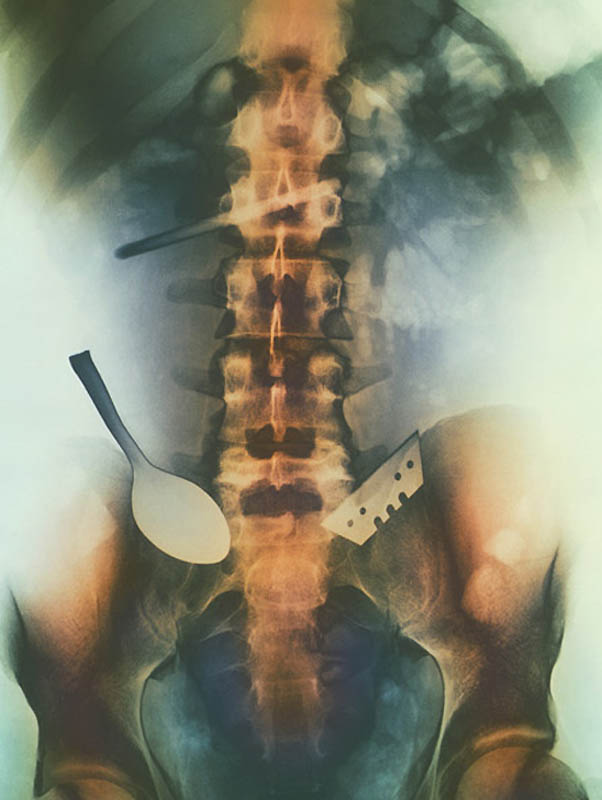

5. Цветной снимок предметов, которые проглотил пациент, и которые застряли в его кишечнике, включая ложку и лезвие.